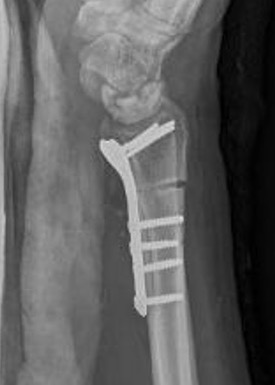

Stage II / IIIA

Radial Shortening +/- vascularized bone graft

Technique

Trimed distal shortening osteotomy plate

Volar approach / bed of FCR

- osteotomy distal to DRUJ

- resection of desired amount

- aim for neutral or +1 mm ulnar variance

- usually 2 - 3 mm

- cutting guides available

- volar plate